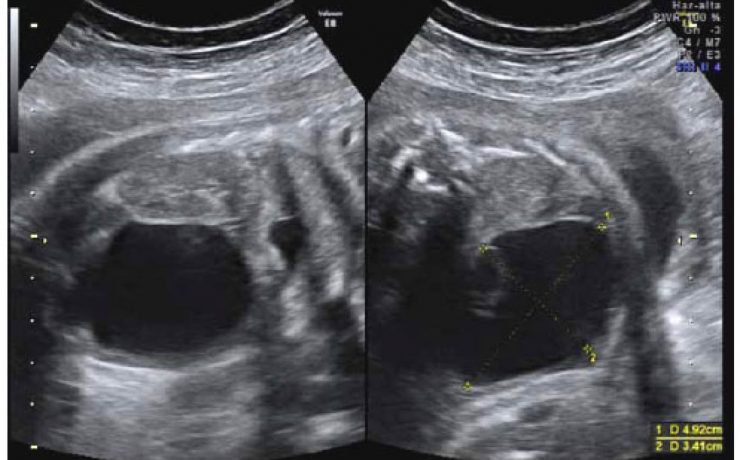

Vesícula biliar y vías biliares

La patología de la vía biliar habitualmente se presenta en la clínica como ictericia o alteración de las enzimas hepáticas, con o sin dolor abdominal o fiebre. La ecografía suele ser la primera prueba de imagen que se realiza, con la intención de discriminar si el paciente presenta una enfermedad